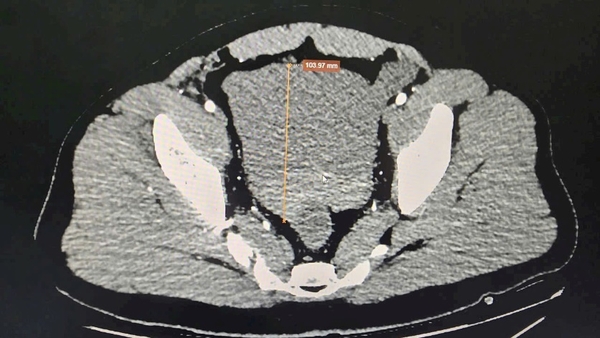

Sau khi hồi sức tích cực, bệnh nhân được chụp cắt lớp vi tính đa dãy (MSCT) ổ bụng và hình ảnh cho thấy: rất nhiều dịch máu trong ổ bụng, nguyên nhân do vỡ giả phình động mạch lách ngay vị trí rốn lách – thủ phạm gây xuất huyết ồ ạt.

-    Sử dụng coil theo kỹ thuật “Sandwich” để nút tắc đoạn động mạch mang giả phình.

Kết quả sau can thiệp: ổ giả phình được bít tắc hoàn toàn, nhu mô lách vẫn được nuôi dưỡng nhờ hệ bàng hệ. Sau 24 giờ, tình trạng bệnh nhân ổn định, không còn dấu hiệu mất máu, dẫn lưu ổ bụng ra khoảng 2 lít máu cũ.